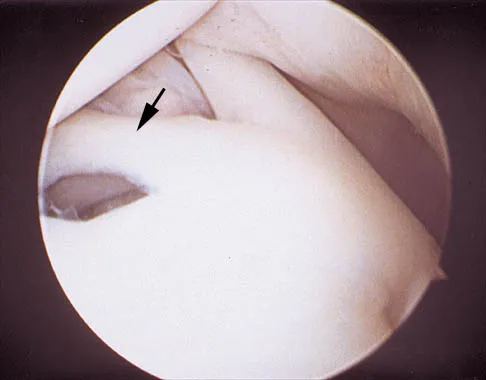

A 24-year-old athlete has a painful right shoulder. Figure 30 shows an intra-articular photograph that was obtained through a posterior portal during arthroscopy; the labrum is indicated by the arrow. Based on these findings, management should consist of

Explanation